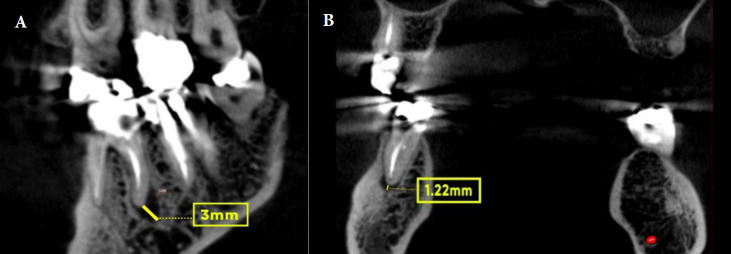

Results: Of the 2053 teeth examined, 14.9% had at least one untreated canal. Untreated canals in teeth increase the chance of having a periapical lesion, raising the prevalence by 11 times. Of these, 91.8% had both untreated canals and periapical lesions. This was more than teeth without untreated canals (35.8%). Most untreated canals were in maxillary molars (65.3%), and mandibular molars (12.54%). There was a statistically significant relationship (P<0.001) between the number of roots, canals, expansion, destruction, and jaw type with the prevalence of untreated canals. The maxillary first molar (68.66%) and second mesiobuccal (MB2) canal (63.27%) had the highest percentages of untreated canals.

Conclusions: The MB2 had the highest prevalence of untreated canals. The presence of untreated canals significantly increased the risk of expansion and/or destruction. Therefore, identifying these conditions can also be useful in diagnosing untreated canals. Dentists should assess the anatomy of the tooth and the structure of the root canal to minimize the possibility of an untreated canal. CBCT can assist in this process.